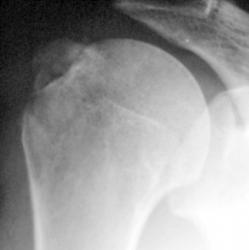

Травма. пациент направлен хирургом в рентгеновский кабинет для рентгенографии плечевого сустава. Были произведены рентгенограммы в двух проекциях. Могу представить, увы, только изображение в прямой проекции.

"Перелом-отрыв бугорка плечевой кости", так любят его наши травматологи, так и называют.

Соглашусь с коллегой Ореховым! Оторвался бугорок!

Ну, и по всей видимости, перелом, без смещения костных отломков.

Насчет линейной тени (две медиальные стрелки) - думаю, не перелом это, закрытая зона роста.

Однозначно, линия, указанная стрелками, это бывшая ростковая зона.

Вот то, что отмечено желтыми стрелочками на последней серии снимков - и есть отрыв большого бугорка. Такой большооооой отрыв большоооооооого бугорка.

Мое мнение, что анатомическая шейка плечевой кости абсолютно интактная! Пациент достаточно молод.